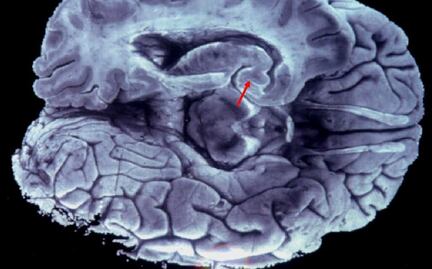

Al comprobar que los animales aumentaron sus niveles de grasa, los científicos confirmaron que es posible actuar sobre esas neuronas sin afectar a otras similares que se localizan en el cebrero.

"El problema es que (esta toxina) puede atravesar la barrera hematoencefálica. En consecuencia, no podemos utilizar esta herramienta molecular para eliminar neuronas periféricas sin afectar a neuronas similares que existen en el cebrero", señala Domingos.

Para hacer frente a este problema, los expertos modificaron químicamente la toxina de la difteria para aumentar su tamaño y limitar su acceso al cerebro, ya que, "normalmente, las moléculas grandes" no pueden cruzar la frontera hematoencefálica, recuerda la investigadora.